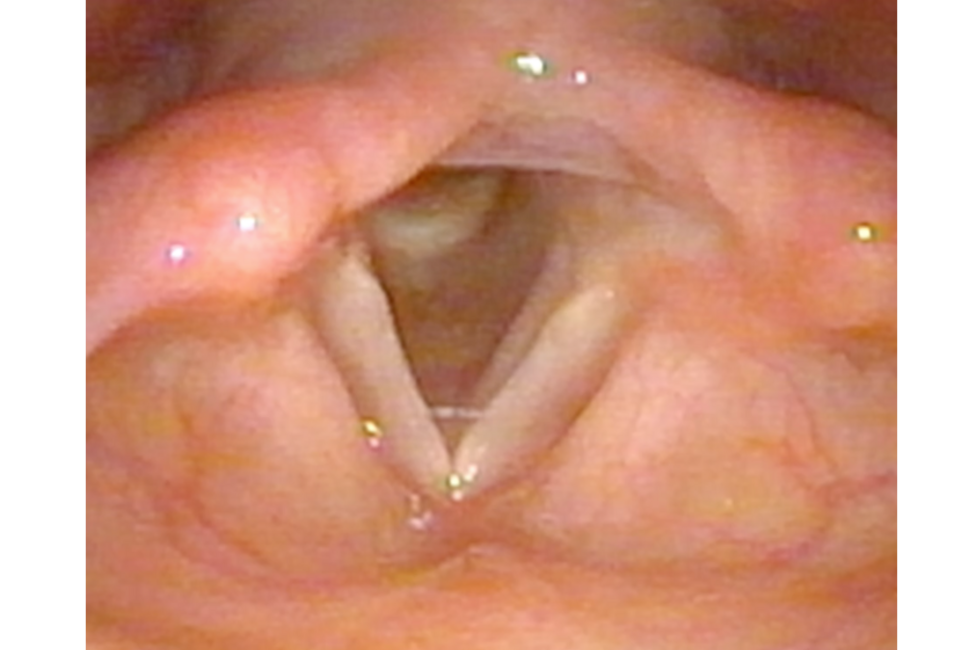

At the Department for Otorhinolaryngology 400 to 500 patients are diagnosed and (surgically) treated each week - amounting to tens of thousands of patients with various clinical pictures each year.